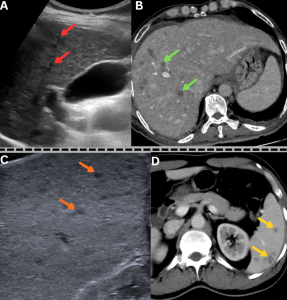

Fig 30: Summary of radiological manifestations of mucormycosis across multiple organ systems.